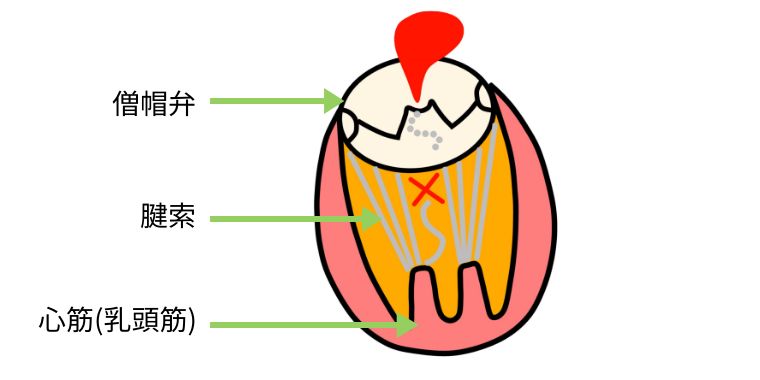

僧帽弁は2つの弁と、心臓から弁を引っ張っている腱索というひも状の部分から成り立っています。手術では、切れた腱索の代わりに新しい人工腱索で補強したり、壊れた部分を切ったり縫い合わせたりして修復した後、弁の周りに特殊なリングを縫いつけて形を整えます。弁置換のようにワーファリンの内服は必要でなく、心臓の機能を温存でき長期成績も良好なため、弁形成術を第一選択としています。